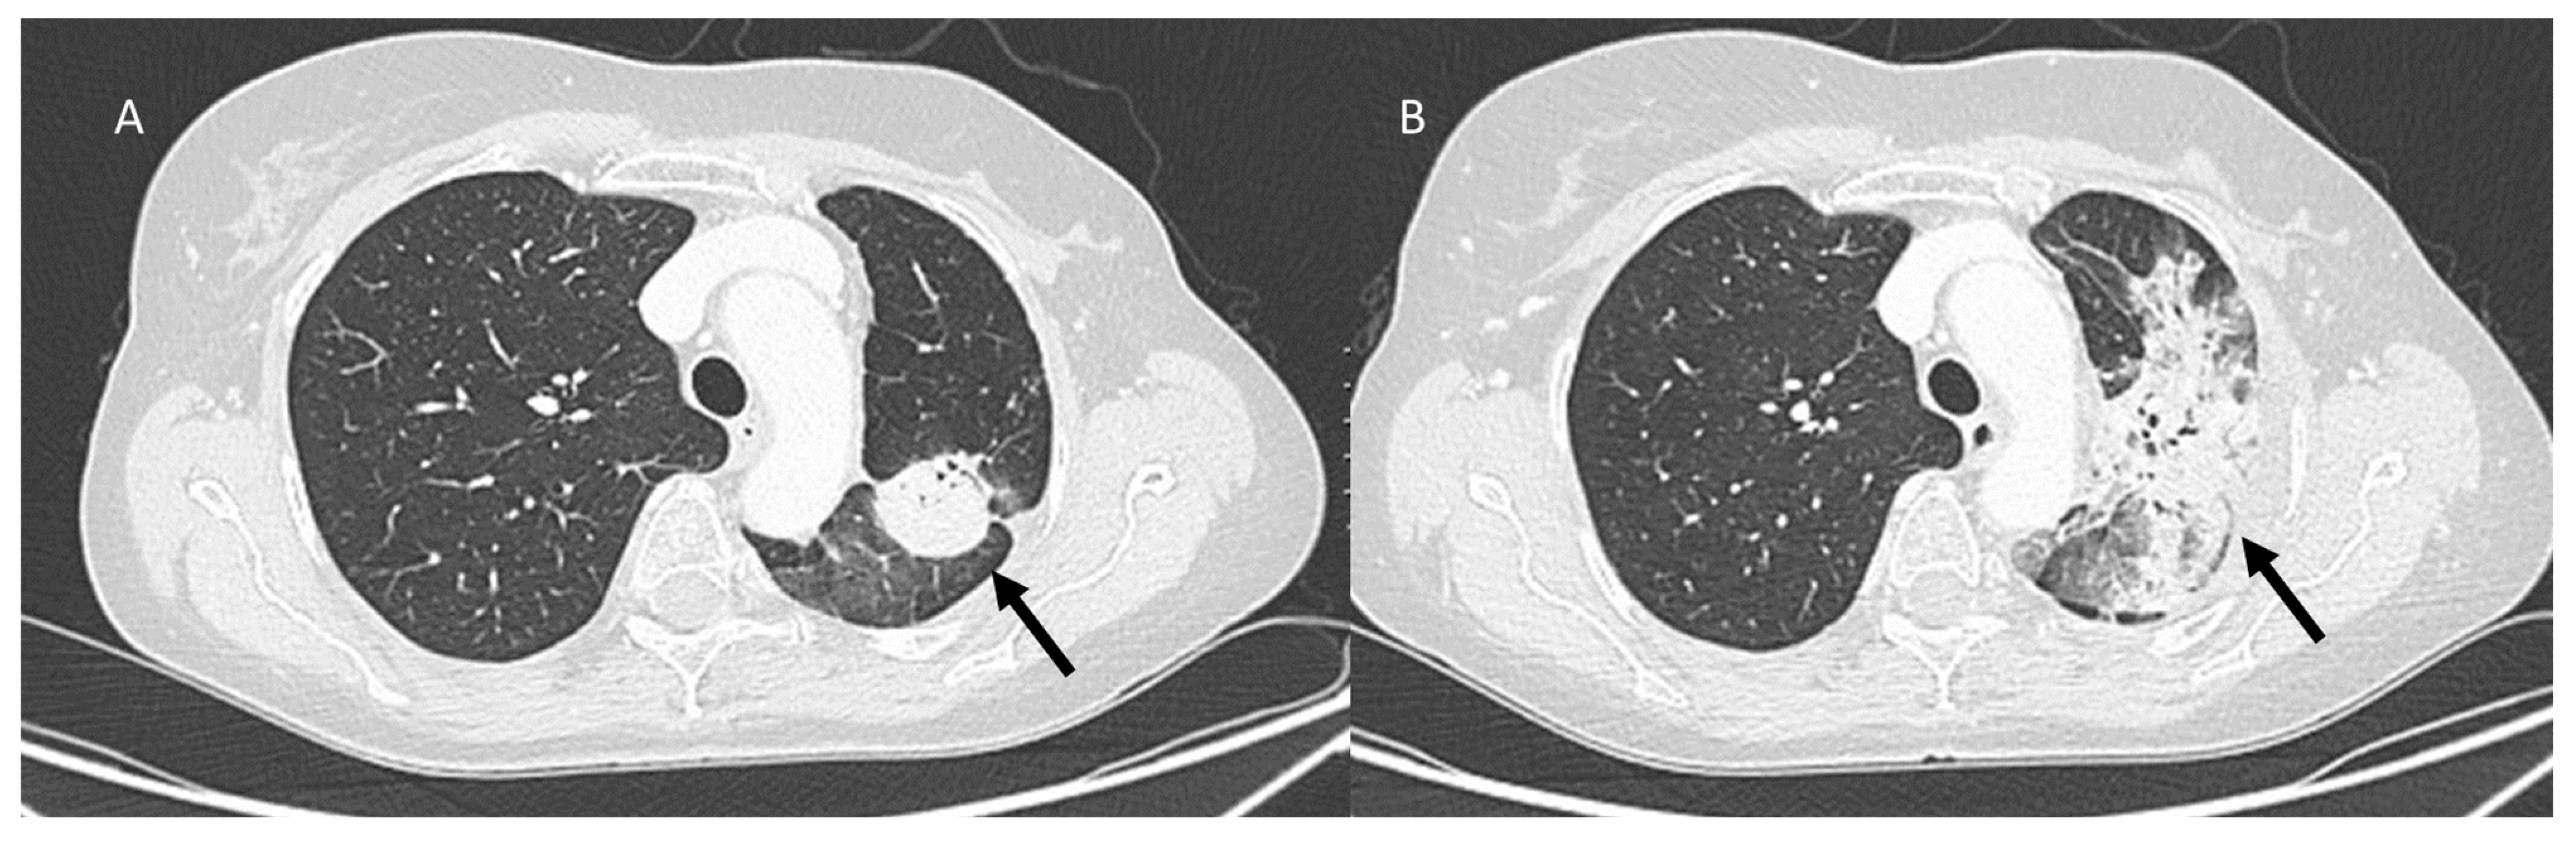

3.5. Progression Disease: Pulmonary Lymphangitis Carcinomatosa

| Pulmonary lymphangitis carcinomatosa | Diffuse (related to the phase of disease) | Irregularly interlobular septal thickening; smooth (early stage) or nodular thickening (late development); ground-glass opacities; pleural effusions. | Tumor spread through lymphatic vessels |